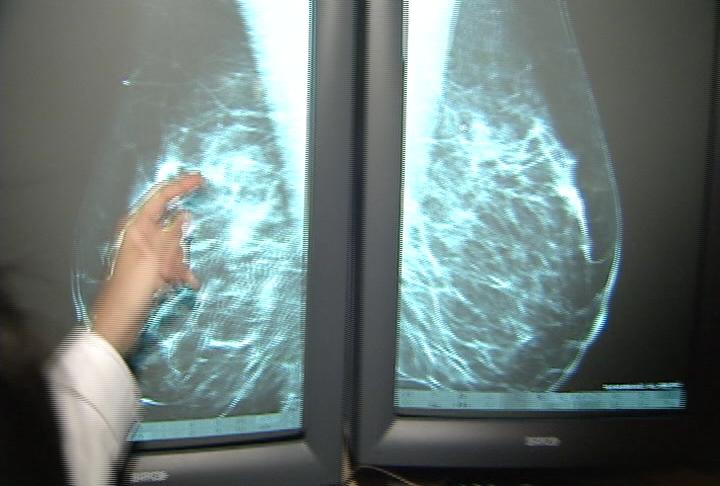

SALT LAKE CITY (AP) -- The number of mammograms women are getting at several Utah hospitals is down.

Screening mammograms at six MountainStar hospitals in Utah are down 22 percent on average. The number was down 14 percent in January over the same month a year ago at Intermountain Healthcare's hospitals statewide.

While health officials say there is always a slight drop around this time of year, they also say a bad economy and last fall's recommendation that women postpone mammograms until age 50 are likely behind the decline.